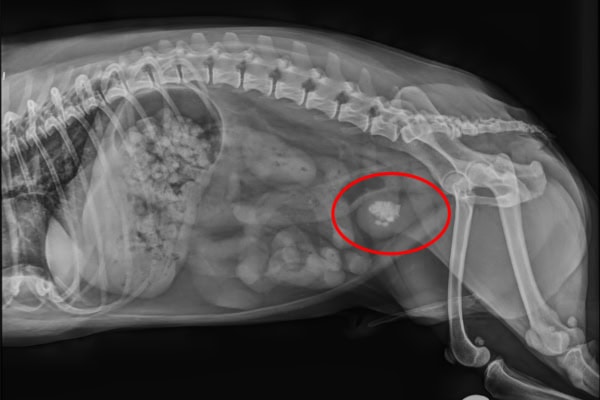

Imaging (X-ray and/or ultrasound)

X-rays can be great for evaluating the size, shape, and number of stones present. Plus, they allow the vet to look for stones in the urethra. Struvite, calcium oxalate, and calcium phosphate stones are easily detected on X-rays. However, xanthine, cystine, and urate stones appear very faint on X-rays and can be easy to miss. It is also important to keep in mind that X-rays may not be able to find uroliths smaller than 3 mm.

Performing a bladder ultrasound allows the vet to visualize all stone types. Additionally, the ultrasound helps the vet to look for bladder cancer in dogs or other abnormalities. However, it is not as accurate as X-rays when it comes to counting stones and evaluating their shape.